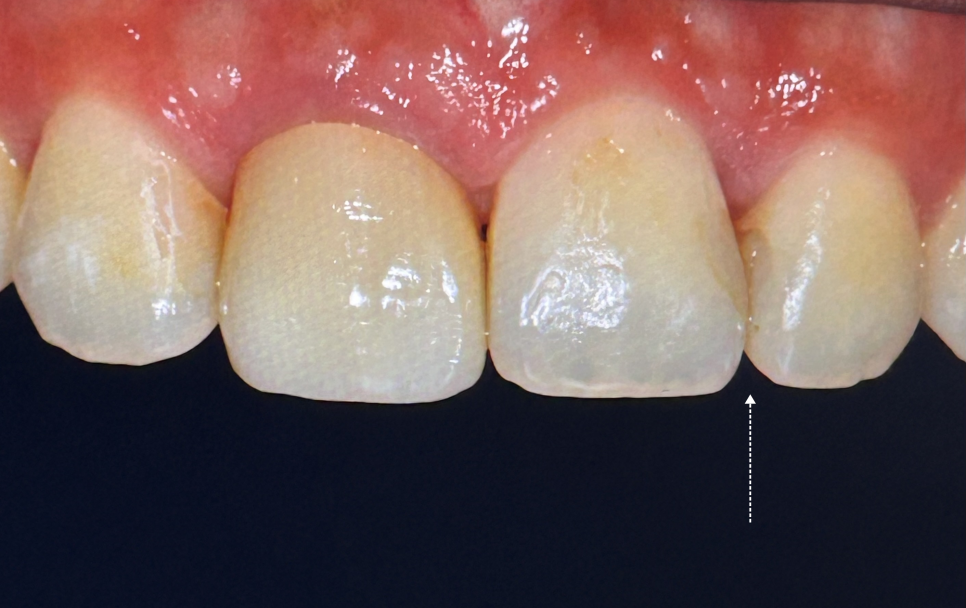

두 달 전, 다른 치과에서 앞니 사이 충치를 레진으로 메꿨는데 표면이 거칠고 빛이 반사될 때 경계가 너무 보이는 게 마음에 걸리셨대요.

또, 표면이 너무 거칠어서 계속 혀로 만지게 된다고 하시더라고요.

확인해 보니 각이져 보이는 느낌이 들었고 거칠었는데요.

문제는 레진의 ‘마감선’이었습니다.

레진과 자연치 경계가 매끄럽지 않았어요.

자연스럽게 보이려면 빛의 굴절, 반사, 곡선 등 다양한 요소들을 고려해야 하죠.

화살표를 표시해둔 곳을 잘 보시면 무슨 느낌인지 아실 거예요.

그중 어느 하나만 삐끗해도 ‘인공적인 느낌’이 나게 돼요.

이분의 경우 그 경계 하나 때문에 계속해서 신경 쓰이셨던 거죠.